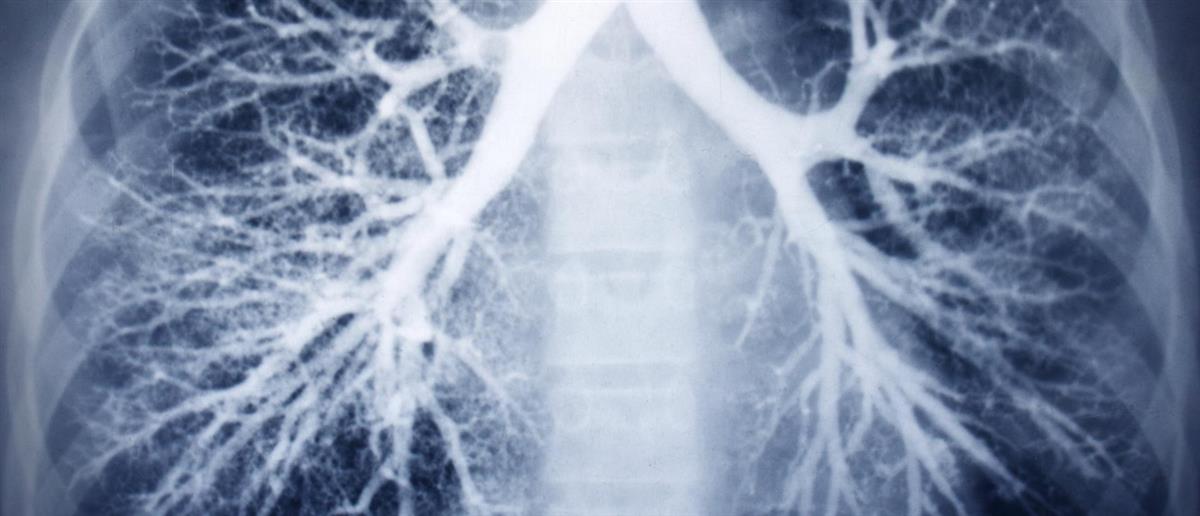

Βρογχεκτασίες

Οι βρογχεκτασίες είναι χρόνια φλεγμονώδης πάθηση των βρόγχων και των βρογχιολίων. Χαρακτηρίζεται παθολογοανατομικά και ακτινολογικά από μόνιμη διάταση των βρόγχων και των βρογχιολίων (διαμέτρου >2mm). Στην παθογένεια των βρογχεκτασιών κρίσιμο ρόλο διαδραματίζει η κινητοποίηση ενός φαύλου κύκλου «λοίμωξης-φλεγμονής» που καθιστά ασθενείς επιρρεπείς σε υποτροπιάζουσες λοιμώξεις.

Η επιβεβαίωση των διάγνωσης των βρογχεκτασιών γίνεται με την αξονική τομογραφία θώρακος υψηλής ευκρίνειας.